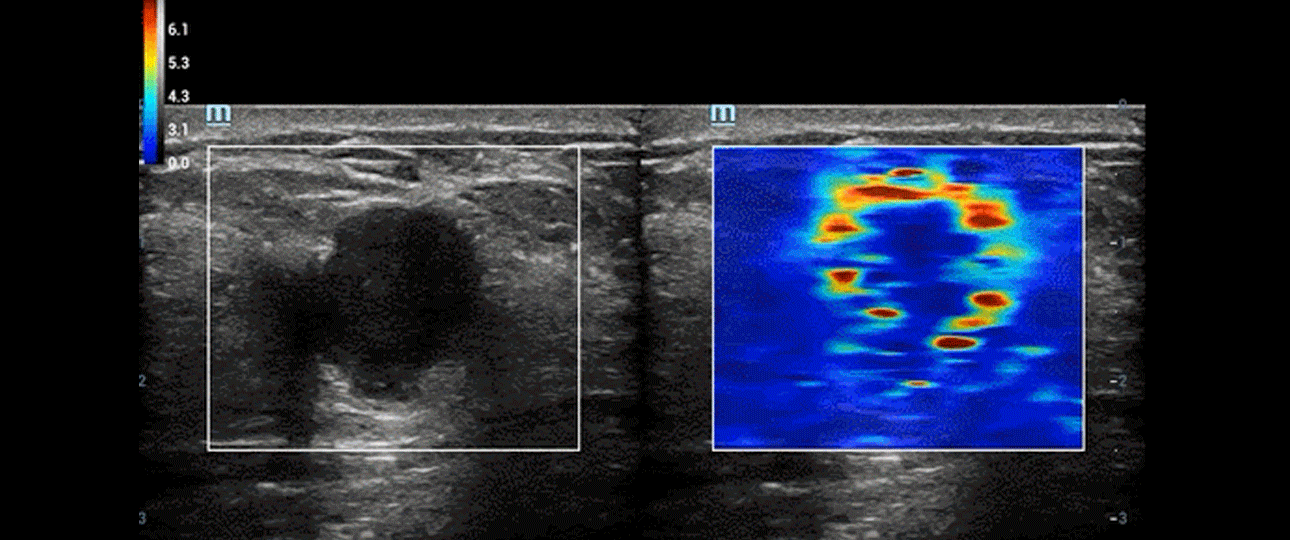

As the case implied, STE can significantly increase the odds of early detection by creating a safe ultrasonic shear wave to disturb soft tissue as it penetrates through the tissue. The ultrasound system can then analyze and evaluate tissue stiffness within a selected region in the scanning area.

pc76-s7

Real time STE

After that, it will interpret and display real-time information in a color-coded image based on the softness and stiffness of the tissue which help to indicate what kind of anomaly is present.

For example, with STE, the possible presence of liver fibrosis can be detected for further follow-up or rule the possibility out by not seeing any stiff tissue.